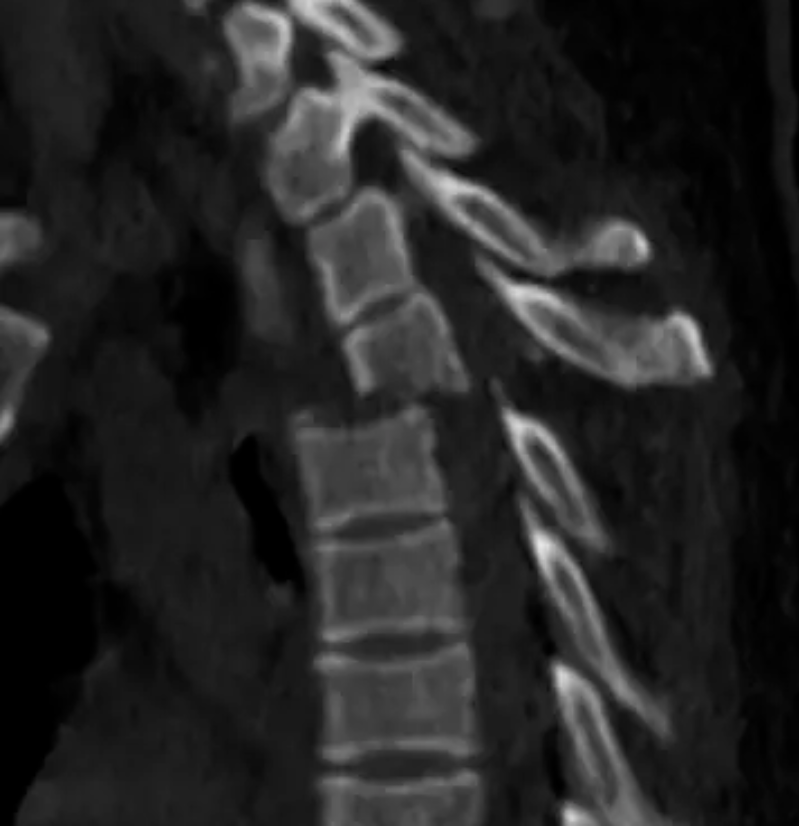

今年6月份,68岁的鲁婆婆(化名)因反复腰痛伴双下肢麻木5年,加重伴右下肢乏力1个月后,到我院康复医学科住院治疗,在药物治疗、康复理疗等治疗效果欠佳的情况下,来到脊柱外科会诊。姚仕奋主任医师仔细查看鲁婆婆的情况及其磁共振片子后发现,胸10、胸12、腰1椎体骨质疏松性压缩骨折,导致鲁婆婆胸腰背部疼痛明显,因胸椎黄韧带骨化并椎管狭窄致双下肢疼痛、麻木、乏力,右下肢肌力下降,双下肢肌张力增高,右下肢膝腱反射亢进,双侧巴氏征阳性,导致鲁婆婆无法行走。

△磁共振提示胸10、胸12、腰1椎体压缩性骨折,胸9/10、胸10/11黄韧带骨化、椎管严重狭窄。